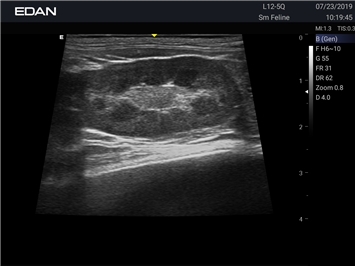

Ветеринарный ультразвук одним нажатием. Система Acclarix AX2 VET разработана с целью обеспечить бескомпромиссную производительность по доступной цене. Наличие уникальных двойных аккумуляторов в легком корпусе массой 4,5 кг из магниевого сплава позволяет системе Acclarix AX2 VET удовлетворять все потребности ветеринарных исследований, сохранив низкую стоимость.

EDAN Acclarix AX2 VET представляет собой специализированную ветеринарную ультразвуковую систему, сочетающую высокую производительность с доступной ценой. Благодаря продуманной конструкции и передовым технологиям, система обеспечивает качественную диагностику животных различных видов.

• Высокое разрешение для детальной диагностики

• Улучшенная визуализация глубоко расположенных органов